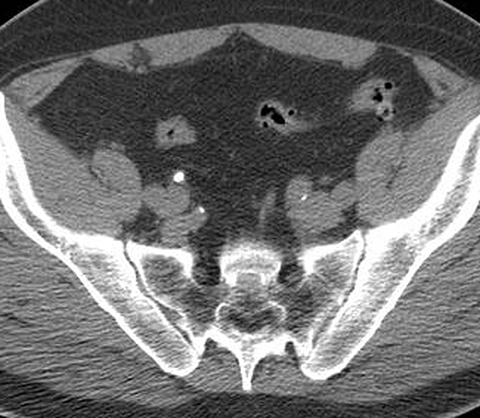

65-year-old male with painless hematuria [3 of 5]